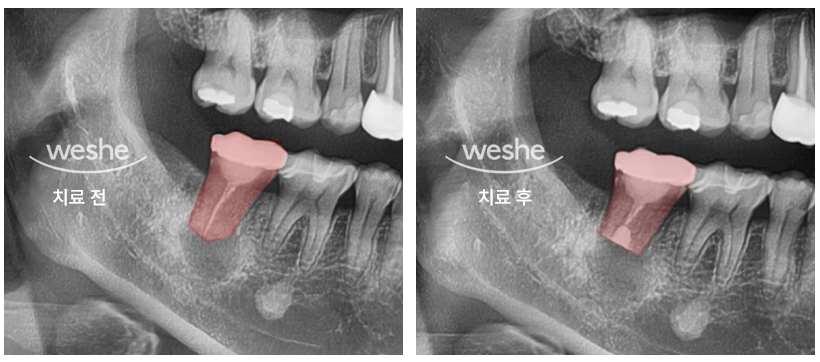

왼쪽 사진은 치료 전, 오른쪽 사진은 치료 직후의 X-ray입니다.

보시면 뿌리 끝이 살짝 짧아졌고,

하얀색으로 채워진 치료제가 보이실 거예요.

“그런데 아직 뿌리 끝에 검은 그림자가 보이는데요?”라고 하실 수도 있습니다.